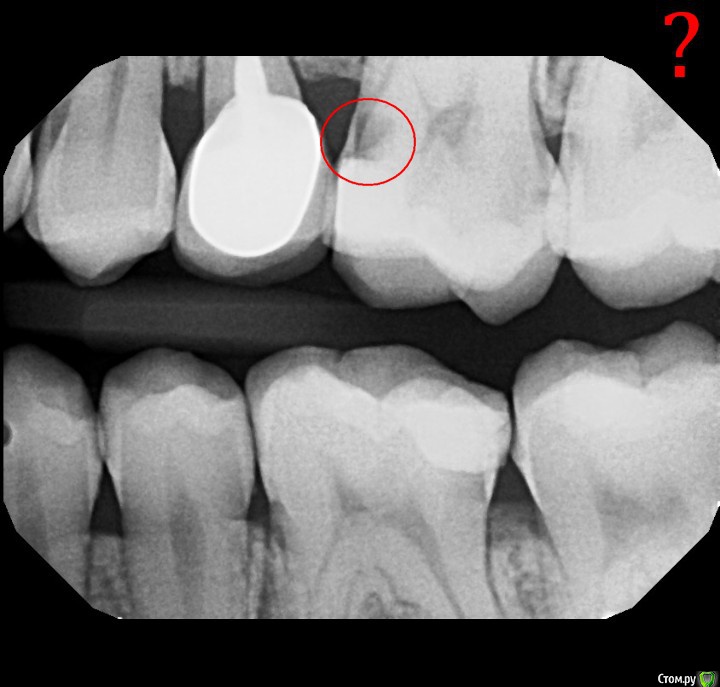

Юлия Сергеевна 85 Опубликовано 18 февраля, 2016 Поделиться Опубликовано 18 февраля, 2016 Коллеги,моей пациентке в Нью Йорке сделали снимки, сказали кариес 4.7 и 2.6.. Сказали коронками обязательно потом покрывать, она хочет сюда прилететь к родственникам и заодно лечить, так как там за все это 3 000 долларов,я вот неуверена по снимкам есть ли там полости. Что скажете? Ссылка на комментарий

Каплан Опубликовано 18 февраля, 2016 Поделиться Опубликовано 18 февраля, 2016 Есть. 4 Ссылка на комментарий

Карен Аванесов Опубликовано 18 февраля, 2016 Поделиться Опубликовано 18 февраля, 2016 может артефакт, а может быть и нет... Жалобы у чуть непострадавшей есть? и какие? Ссылка на комментарий

Карен Аванесов Опубликовано 18 февраля, 2016 Поделиться Опубликовано 18 февраля, 2016 Ясно. Вы хотите сильно видеть подругу? кариеса там нет. это артефакт. посмотрите внимательно на костную ткань. Ссылка на комментарий

ЕленаВалерьевна Опубликовано 19 февраля, 2016 Поделиться Опубликовано 19 февраля, 2016 я тоже думаю что есть. на 4.7 дистально, 2.6 медиально. конечно лучше бы еще во рту посмотреть, прежде чем так однозначно утверждать. да пусть приезжает, и с родными встретится, и если нужно, полечится) Ссылка на комментарий

M@estro Опубликовано 19 февраля, 2016 Поделиться Опубликовано 19 февраля, 2016 А 3.6 никого не смущает? 2 Ссылка на комментарий

Гарриевич Опубликовано 19 февраля, 2016 Поделиться Опубликовано 19 февраля, 2016 Так и не скажешь, вроде есть. Но при осмотре может окажется что и нетСнимки очень контрастные Ссылка на комментарий

Zlata-doctor Опубликовано 24 февраля, 2016 Поделиться Опубликовано 24 февраля, 2016 http://s019.radikal.ru/i600/1602/a9/7c45f3051e32.pnghttp://s019.radikal.ru/i618/1602/4d/322cf4914262.png 4.7-как бы не пульпит ( в любом случае контроль через несколько мес после лечения)-полость под экватором и сглажен рог пульпы=раздражена4.6 апроксимальный кариес????4.5-дистальная поверхность??????????1.6 -подозрительная щель в области пломбы медиальной поверхности????2.6 медиальная поверхность под пломбой, дистально возможно, тоже есть ИТОГО2.6 и 4.7 лечение, остальное уточнять, скопировать, или динамическое наблюдение Ссылка на комментарий